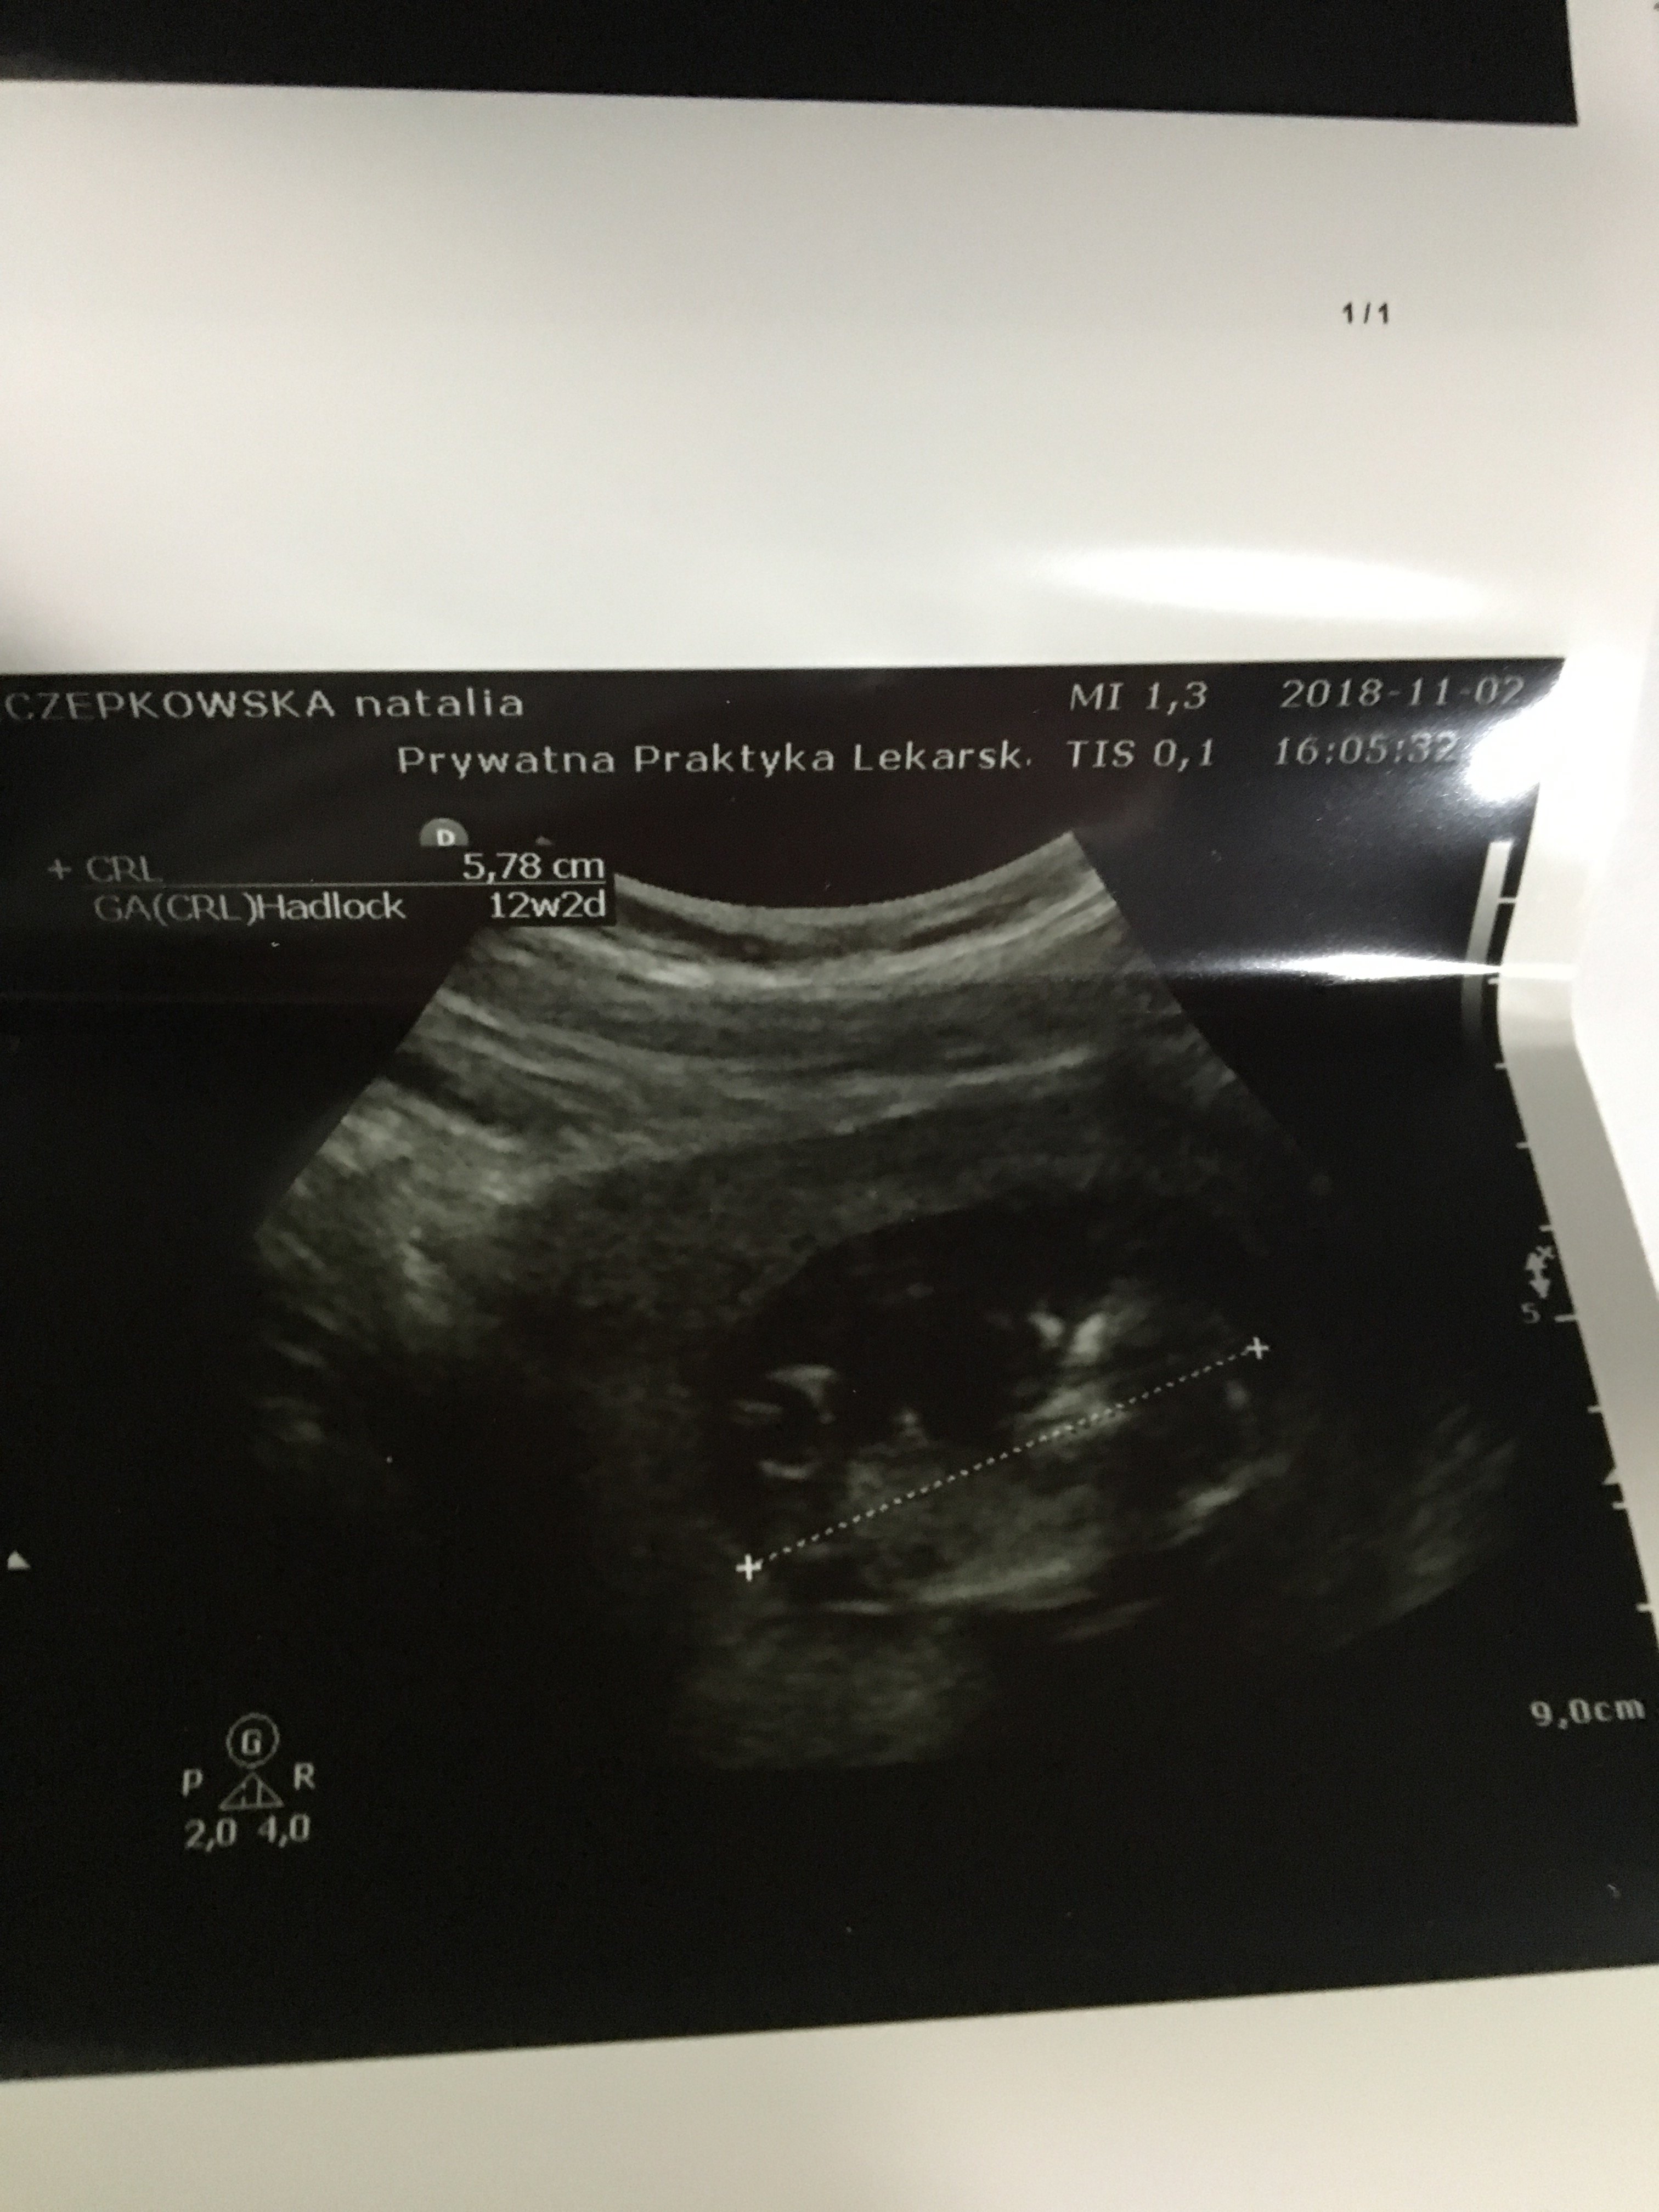

Witam w 19 tygodniu ciąży dowiedziałam się ze będę miała dziewczynkę w 20 tyg okazało się jednak , że to chłopak. Sama już nie wiem bo na jednym usg widać na pewno dziewuche a na drugim chłopca. Może to pempowina ?? Może ktoś mi pomoże rozwiązać ta zagadkę

no nic , zobaczymy na kolejnym USG. To doswiadczona Pani wiec chyba wie co mówi a ja ogladam zdjęcia pod każdym kątem i szukam śladów kobiecych